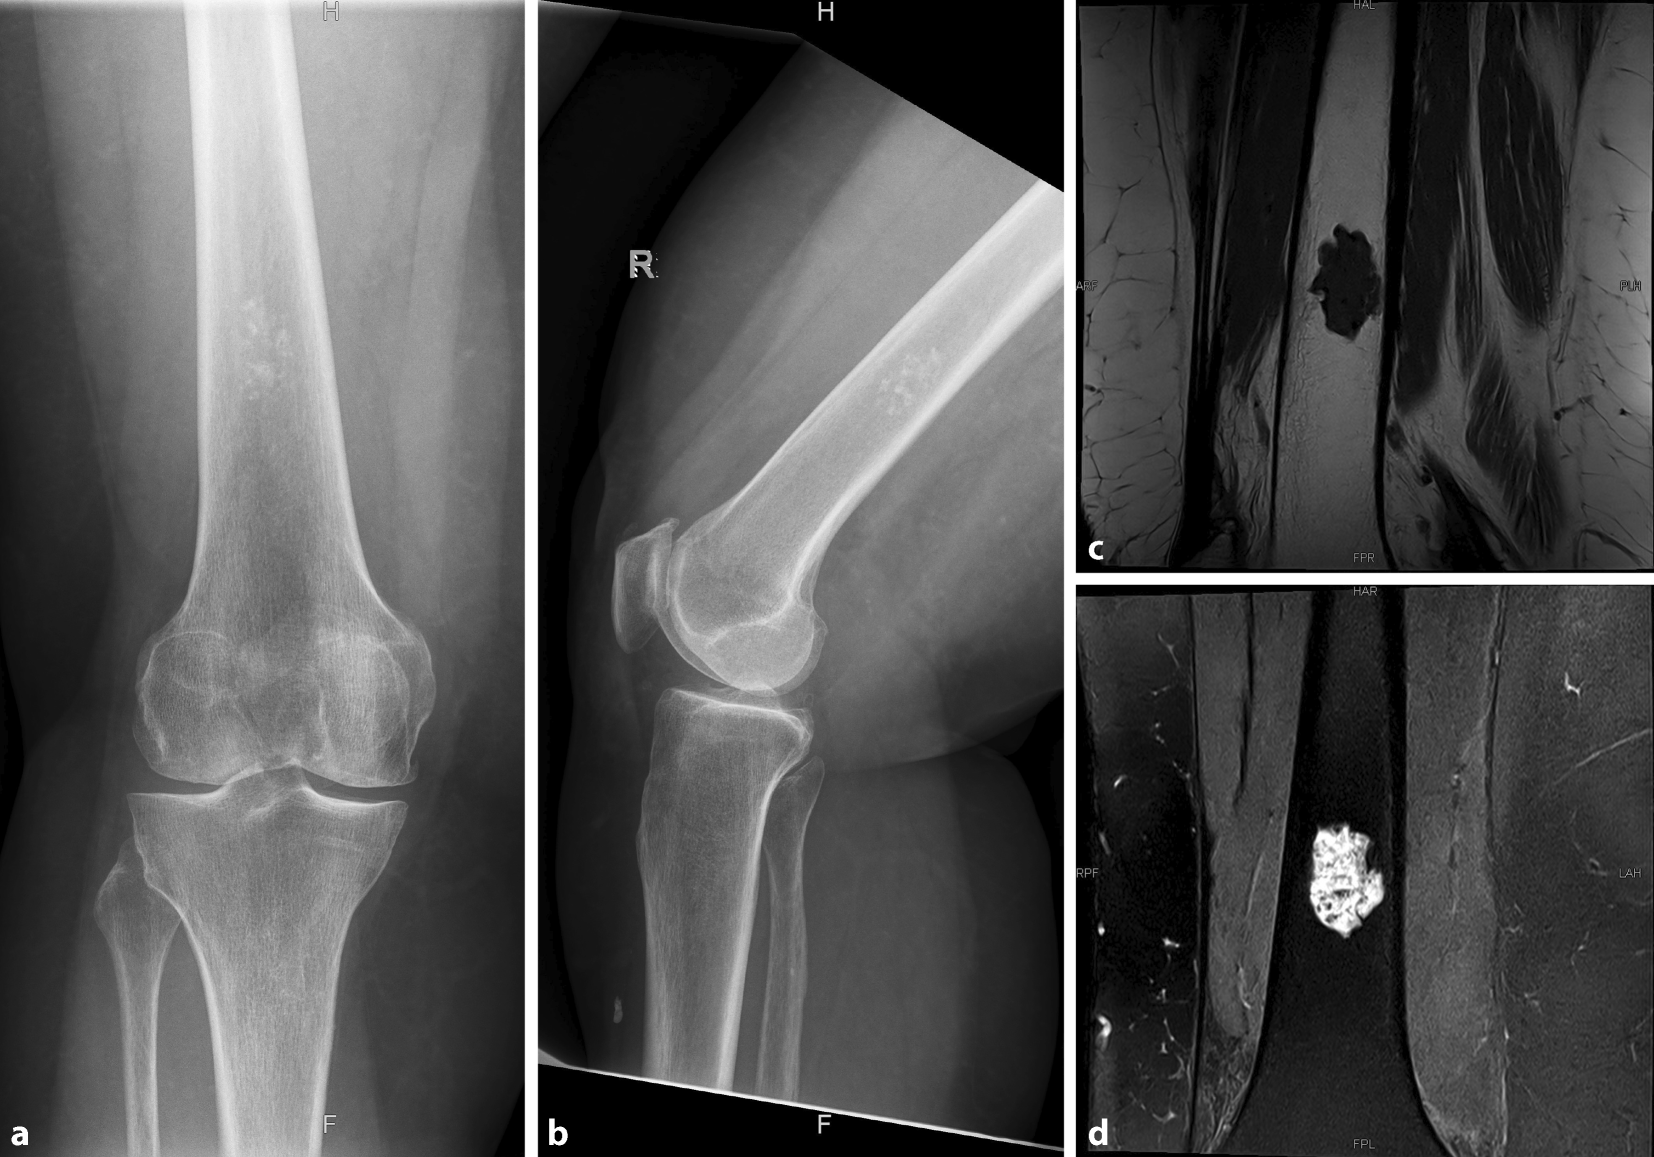

Bei einer 69-Jahre alten Patientin wurde aufgrund von Schmerzen am rechten Kniegelenk eine Röntgenuntersuchung durchgeführt. Es waren typische Zeichen einer Gonarthrose mit subchondraler Sklerosierung, Gelenkspaltverschmälerung, und osteophytäre Randanbauten nachweisbar (Abb. 1a, b). Darüber hinaus zeigte sich in der distalen Femurdiaphyse eine zentral gelegene, nichtrandsklerosierte Läsion mit diskreter, „popcornartiger“ Verkalkung ohne eindeutigem Hinweis auf Knochendestruktion, Periostreaktion, Kortexarrosion oder extraossären Anteilen (Abb. 1a, b).

Abb. 1

Röntgenbild des rechten Kniegelenks a. p. (a) und seitlich (b) einer 69-jährigen Patientin, das einen zentral liegenden, popcornartig verkalkten chondrogenen Tumor zeigt. In Zusammenschau mit der MRT (c sagittal, T1 TSE; d koronar, Proton Density [PD] Turbo Spin Echo [TSE] Fett Sat [FS]), die eine zentral im Markraum lokalisierte, gut demarkierte Läsion ohne Scalloping oder umgebendes Knochenmarksödem zeigt, handelt es sich um ein Enchondrom

Bei bildgebendem Verdacht auf das Vorliegen eines chondrogenen Tumors wurde weiterführend eine MRT durchgeführt. In dieser zeigte sich, analog zur Röntgenbildgebung, in der distalen Femurdiaphyse rechts eine in T1 hypointense (Abb. 1c) und in der protonengewichteten, fettunterdrückten Sequenz hyperintense Raumforderung (Abb. 1d) mit zentralen Verkalkungsarealen und einer Größe von 3 cm (kraniokaudal, c.c.) × 2 cm (mediolateral, m.l.) × 2 cm (anteroposterior, a. p.). Es lag kein umgebendes Knochenmarködem und kein endostales Scalloping vor (Abb. 1c, d).

In Zusammenschau von Röntgenbild und MRT wurde die Verdachtsdiagnose eines Enchondroms gestellt

In Zusammenschau von Röntgenbild und MRT wurde die Verdachtsdiagnose eines Enchondroms gestellt. Die Schmerzen wurden auf die Gonarthrose zurückgeführt. Da es bildgebend keinen sicheren Hinweis auf aggressives Verhalten gab (siehe unten), wurde keine ergänzende Kontrastmittel-MRT durchgeführt. Es wurde eine bildgebende Verlaufskontrolle in einem Jahr, erneut mit MRT, empfohlen. Im Fall der Implantation einer Knietotalendoprothese empfehlen wir die Verwendung von patientenspezifischen Schnittblöcken, die keine intramedulläre Ausrichtung benötigen und so einen Kontakt mit dem chondrogenen Tumor vermeiden.